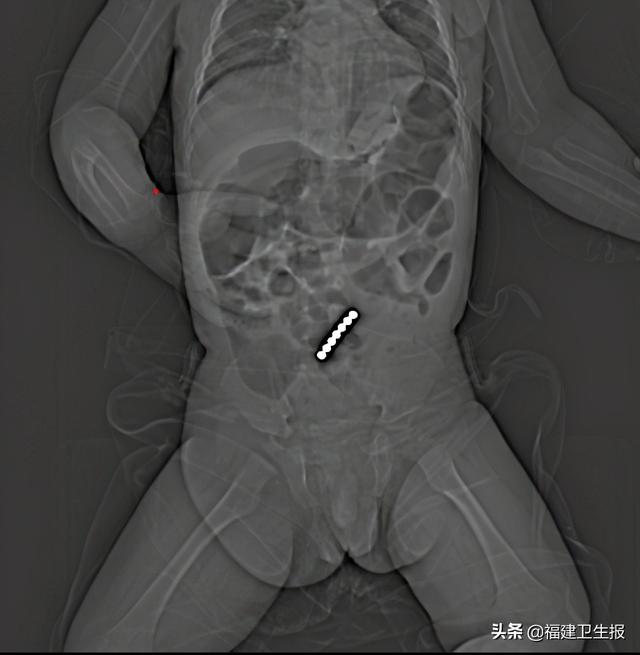

入院后 , 医生在为贝贝做CT检查时发现 , 其腹部出现“七星连珠”的图案 , 判断贝贝的症状系腹中存在消化道异物 , 进而导致肠道穿孔和肠系膜穿透伤 。 随即贝贝住进宁德市闽东医院胃肠、小儿外科 。

术中 , 医生探查发现 , 贝贝的消化道异物为7颗直径约2毫米的磁力珠 , 已致3处小肠穿孔、1处小肠系膜穿透伤 。 医生通过手术 , 顺利将7颗磁力珠取出 , 并修补好穿孔处 。 术后 , 孩子已脱离危险 。